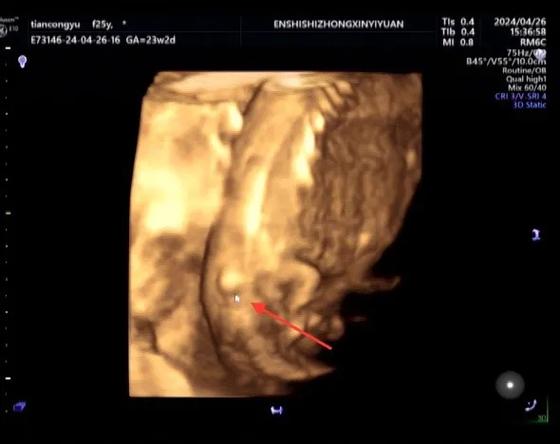

大排畸检查(通常在孕20-28周之间做,最佳时间是22-26周)是通过B超观察胎儿各个器官结构是否发育正常,脊柱是一个结构相对复杂、且需要特定切面才能看清的部位,导致“看不清”的原因有很多,其中大部分是客观因素,而非胎儿本身有问题:

- 胎背朝外:如果胎儿的背部正对着妈妈的肚皮,B超医生就无法清晰地看到脊柱的完整结构,就像我们从背后看一个人的脊椎,只能看到轮廓,看不清细节。

- 姿势固定:胎儿可能一直保持着一个蜷缩、趴着或者侧卧的姿势,导致脊柱的某些节段被肢体、胎盘或脐带遮挡。

(图片来源网络,侵删)- B超医生的经验和设备:虽然大排畸是标准检查,但不同医生的经验和医院的设备先进程度也可能存在差异,一个经验丰富的医生会花更多时间尝试变换体位来寻找最佳切面。

在绝大多数情况下,“脊柱没看清”的首要原因是胎儿不给力,不配合检查,而不是宝宝真的有脊柱问题。